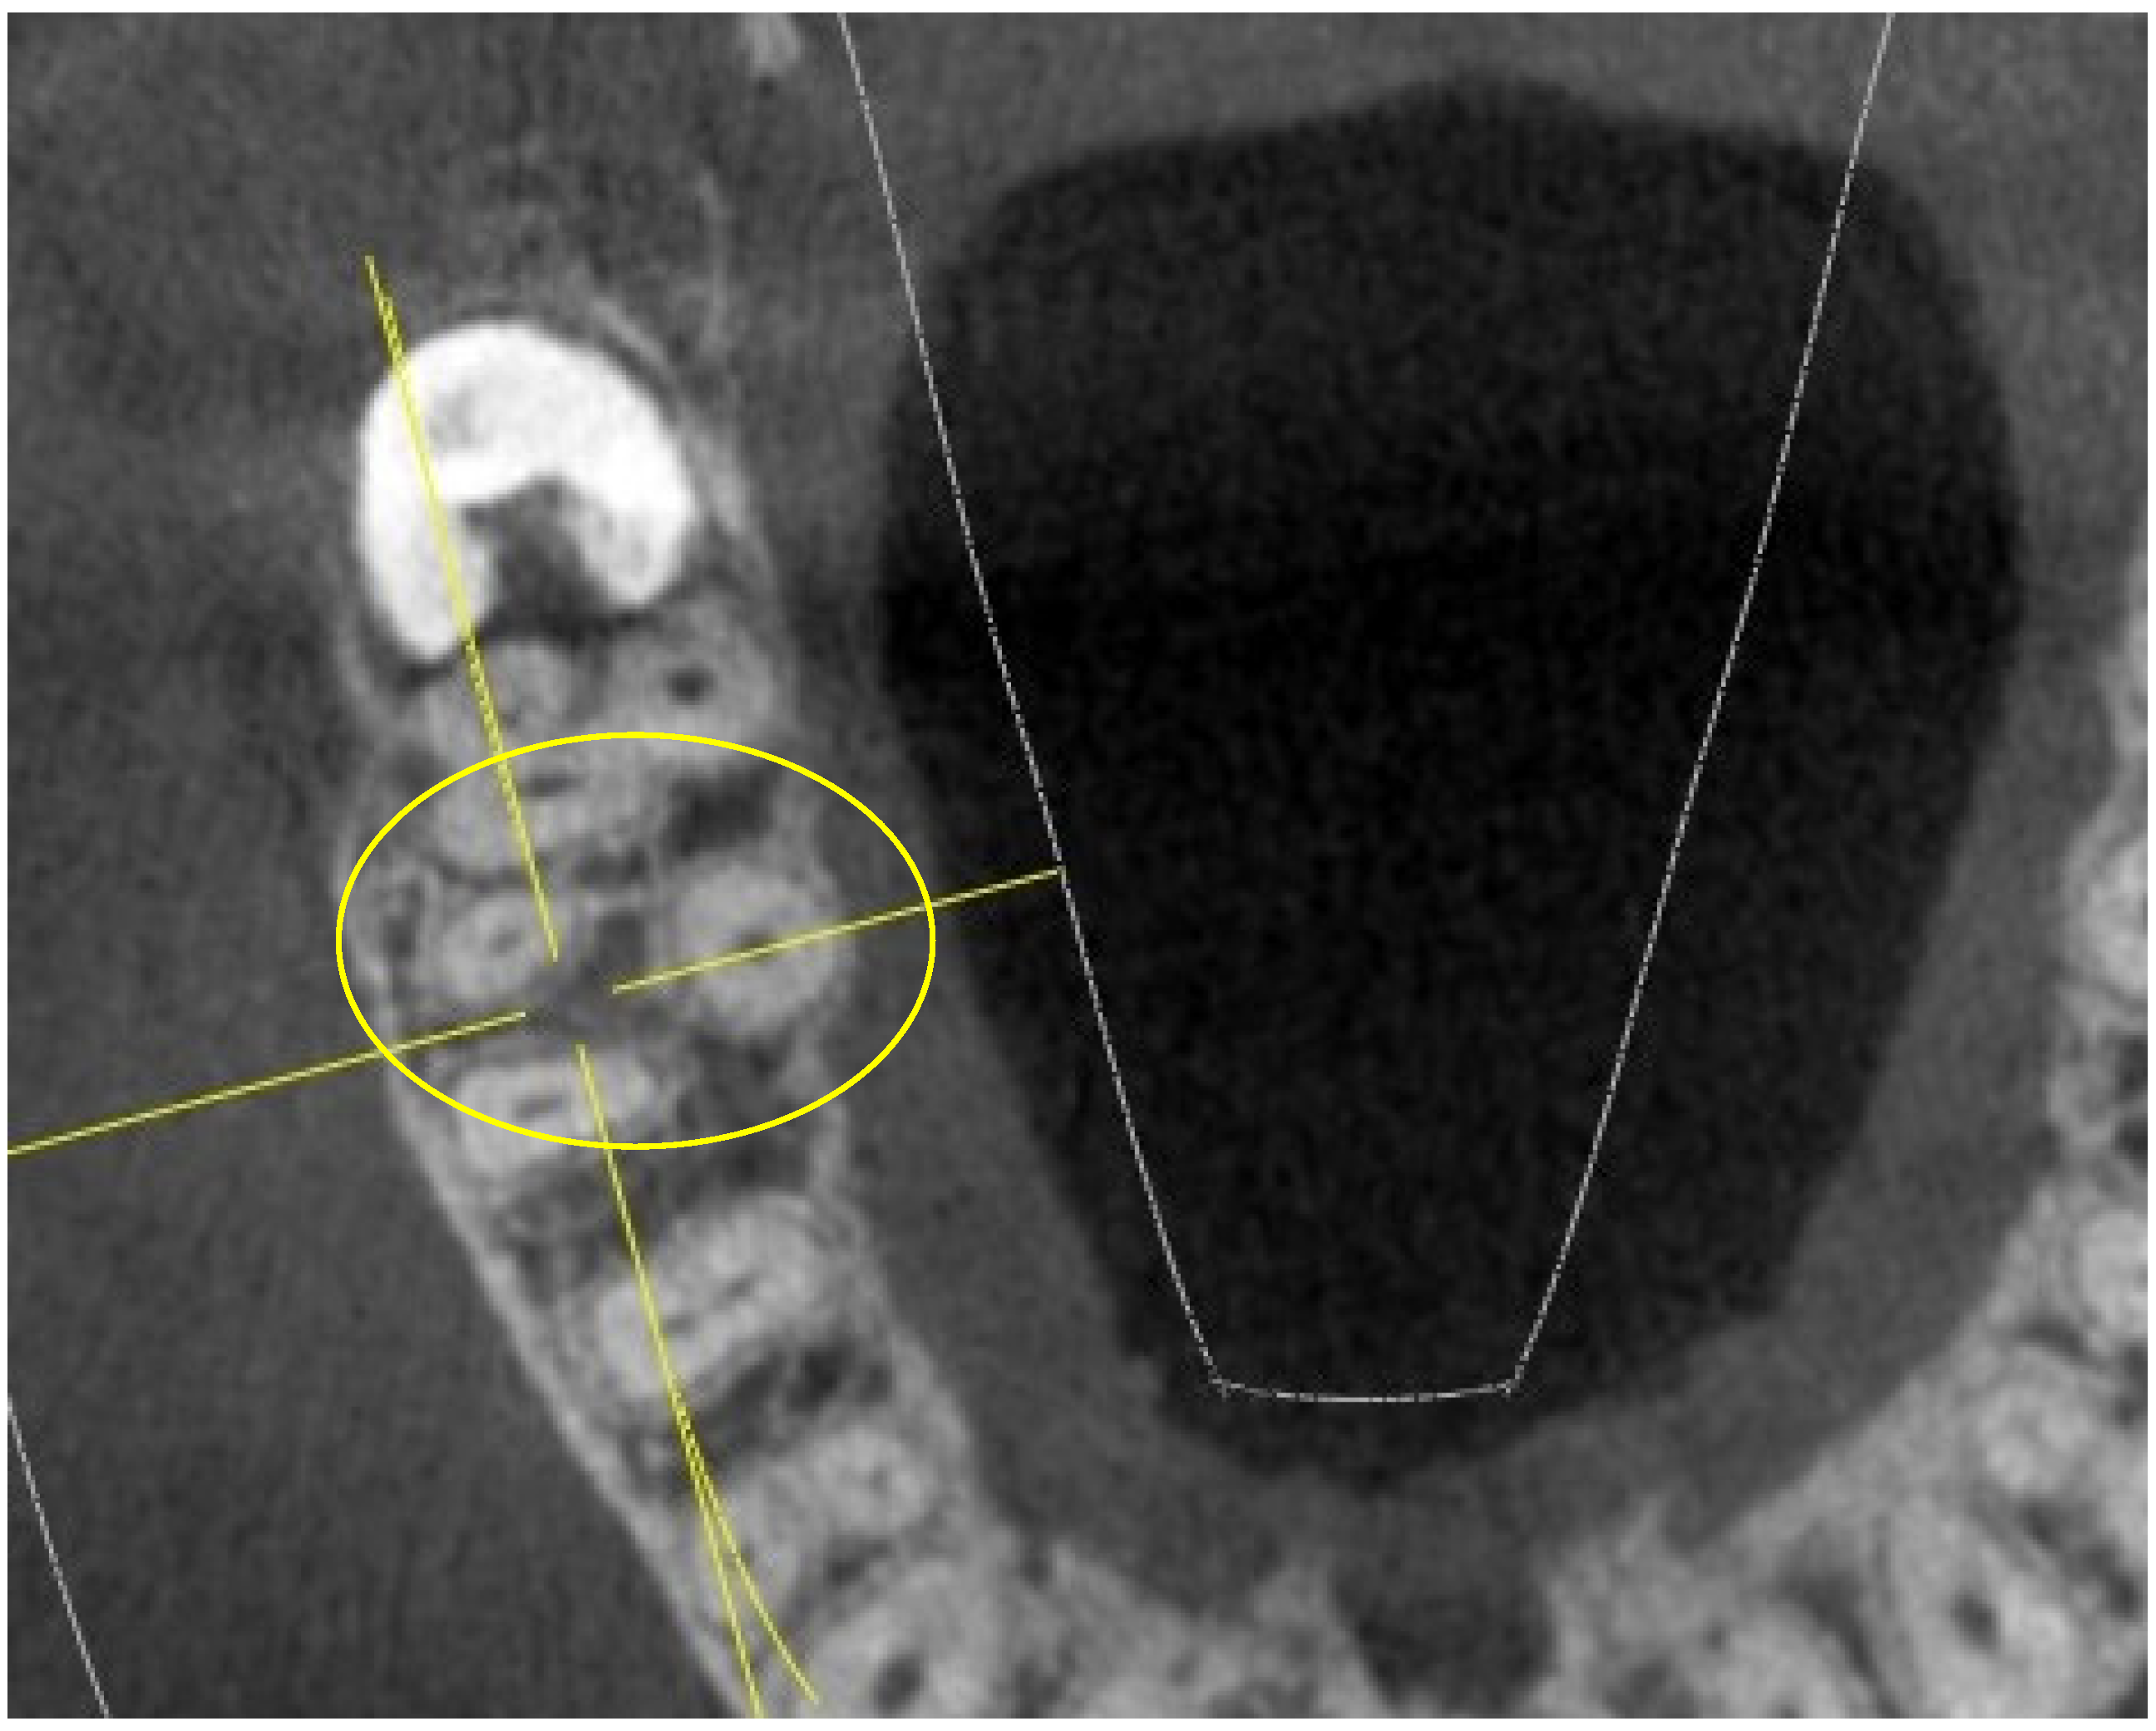

- shape of the pulp chamber associated with a letter of the alphabet (in relation to the number and arrangement of canal orifices);

- K: in maxillary molars with the presence of four canal orifices: MB, MB-2, disto-buccal and palatal; a line joining the disto-buccal and palatal and two other lines radiating from the center of this line to MB and MB-2, forming the letter “K” of the alphabet.

- Y: in maxillary molars with three canal orifices: MB, disto-buccal and palatal; when a line is formed joining the three canals in the center of the access cavity, it resembles the letter “Y” of the alphabet.

| Shape | K(20), Y(4), I(2) | K(16), Y(9), I(1) | K(23), Y(2), I(1) | K(11), Y(12), I(3) | ||||||